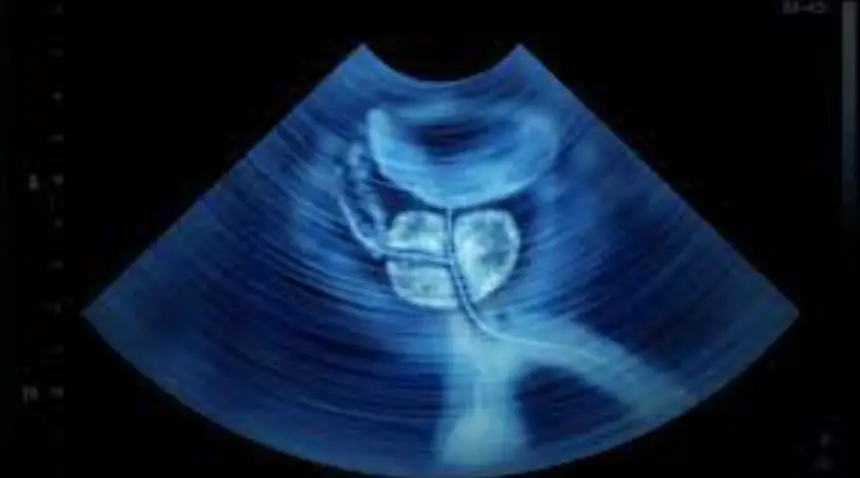

حقق باحثون من جامعتي رايس وفاندربيلت في الولايات المتحدة تقدمًا واعدًا في علاج سرطان البروستاتا، حيث تمكنوا من تقليص حجم الأورام باستخدام مزيج مبتكر يجمع بين علاج جزيئي صغير (TRAIL) والموجات فوق الصوتية المركزة (FUS)، وفقًا لدراسة نُشرت في مجلة Advanced Science.

وتكمن أهمية هذا الابتكار في استهداف الأورام بدقة دون الحاجة إلى تدخل جراحي، مما يقلل من الآثار الجانبية مقارنة بالعلاجات التقليدية. ويأتي ذلك في ظل الحاجة الملحة لعلاجات أكثر كفاءة لهذا المرض، الذي يُعد ثاني أكثر أسباب الوفاة المرتبطة بالسرطان لدى الرجال في الولايات المتحدة، كما أنه أكثر أنواع السرطان انتشارًا في أكثر من 100 دولة.

ويواجه علاج (TRAIL) تحديًا رئيسيًا يتمثل في قصر عمره داخل مجرى الدم، حيث لا يتجاوز تأثيره 30 دقيقة، مما يتطلب تكرار الجرعات. في المقابل، تعمل تقنية (FUS) على استهداف الخلايا السرطانية داخل الجهاز الدوري لكنها لا تعالج الأورام الصلبة بشكل فعال. غير أن الجمع بين القوى الميكانيكية للموجات فوق الصوتية وعلاج (TRAIL) أظهر نتائج واعدة، حيث ساهم هذا النهج في تقليص عدد الخلايا السرطانية وحجم الأورام بشكل كبير مقارنة باستخدام أي من العلاجين بمفرده.